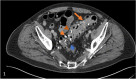

Background: Barium sulfate is utilized for imaging of the gastrointestinal tract and is usually not deposited within the wall of the intestine. It is thought that mucosal injury may allow barium sulfate to traverse the mucosa, and allow deposition to occur uncommonly. Most pathology textbooks describe the typical barium sulfate deposition pattern as small granular accumulation in macrophages, and do not describe the presence of larger rhomboid crystals. This review will summarize the clinical background, radiographic, gross, and microscopic features of barium sulfate deposition in the gastrointestinal tract. A review of the PubMed database was performed to identify all published cases of barium sulfate deposition in the gastrointestinal tract that have been confirmed by pathologic examination.

Conclusions: A review of the literature shows that the most common barium sulfate deposition pattern in the gastrointestinal tract is finely granular deposition (30 previously described cases), and less commonly large rhomboid crystals are seen (19 cases) with or without finely granular deposition. The fine granules are typically located in macrophages, while rhomboid crystals are usually extracellular. There are various methods to support that the foreign material is indeed barium sulfate, however, only a minority of studies perform ancillary testing. Scanning electron microscopy with energy dispersive X-ray spectroscopy (SEM/EDS) can be useful for definitive confirmation. This review emphasizes the importance of recognizing both patterns of barium sulfate deposition, and the histologic differential diagnosis.